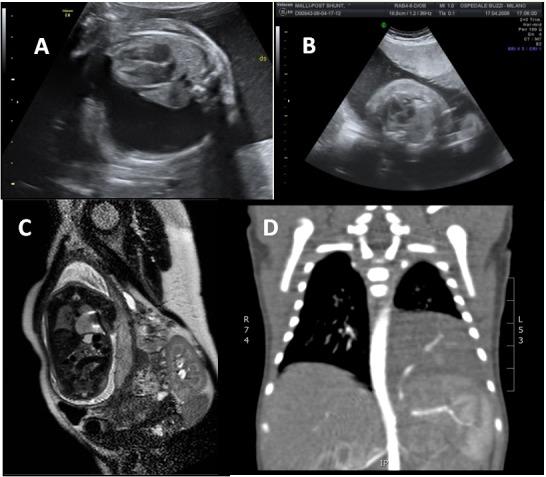

We retrospectively reviewed all prenatally diagnosed PM patients referred to our Centre in the period between January 1999 and December 2014. All cases were diagnosed by one of our Maternal-Fetal Specialists by US examination. Congenital pulmonary airway malformation (CPAM) volume ratio (CVR), development of fetal complications, need for fetal therapy, need for neonatal resuscitation and timing of surgery were analyzed.

A total of 70 fetuses were diagnosed with a PM in the period of study. An initial CVR higher than 1.6 was found in 16/70 patients (22.8%); 14/16 developed fetal complications (p less than .0001). Fifty-six fetuses (80%) did not develop any complications during pregnancy. To all complicated cases a prenatal treatment was offered, carried out in 12 (1 termination, 1 refusal). Survival rate was 100%. Sixty-three fetuses (90%) were asymptomatic at birth and did not require any neonatal resuscitation. Six patients submitted to fetal therapy and one untreated presented with neonatal respiratory distress, required mechanical ventilation at birth and early surgery in the neonatal period (7/70, 10%).

CVR > 1.6 and the presence of fetal complications can be considered as predictors of respiratory distress at birth and of the need for early surgery. Nevertheless, the vast majority of PM are asymptomatic at birth and only a small group of fetuses require prenatal and postnatal treatment and support.